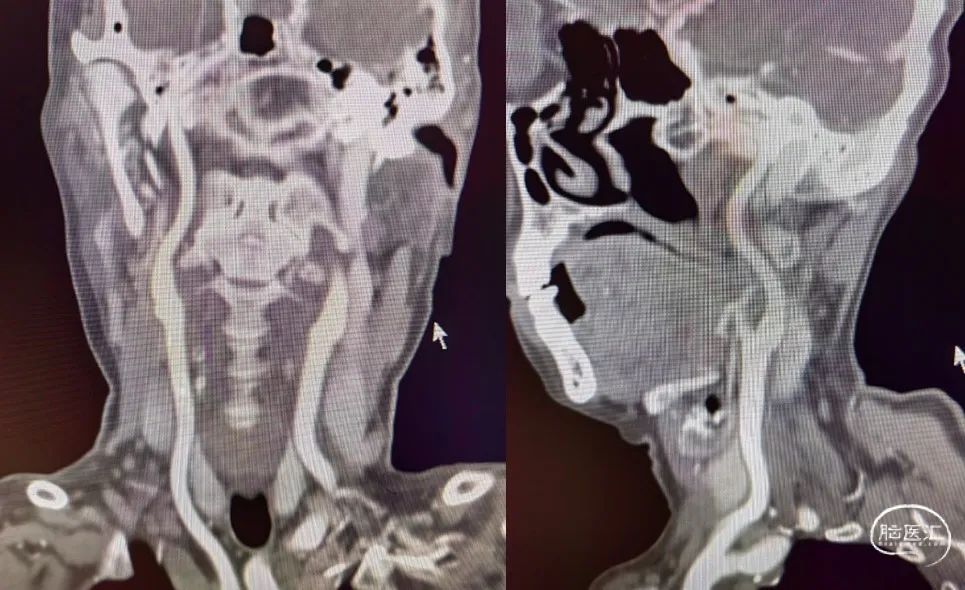

重要影像结论:右侧颈内动脉岩骨段管腔内不清晰,眼动脉段远端管腔较对侧明显缩小。

重要影像结论:右侧ICA起始部急性闭塞,前交通动脉、后交通动脉未开放。

6F-远端通路导管在黑泥鳅导丝的指引下通过闭塞段送至眼动脉段,造影证实闭塞段在海绵窦段,予以ADPAT技术取出少量血栓,仍未开通。

通过微导管释放取栓支架,SWIM取栓技术,可见海绵窦段狭窄,前向血流不稳定。